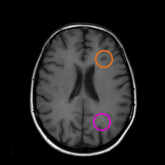

An MRI scan is an important tool used to help confirm an MS diagnosis. There are 2 types of MRI scans used to see lesions:

T1-weighted MRI scans with gadolinium highlight only active lesions. An orange circle points out Black hole while a purple circle points out Gd T1-w lesions.

T1-weighted scans with gadolinium highlight only active lesions. Gadolinium is a coloring that’s injected in the body to help healthcare providers see new and active lesions.

Black holes Gd T1-w lesions